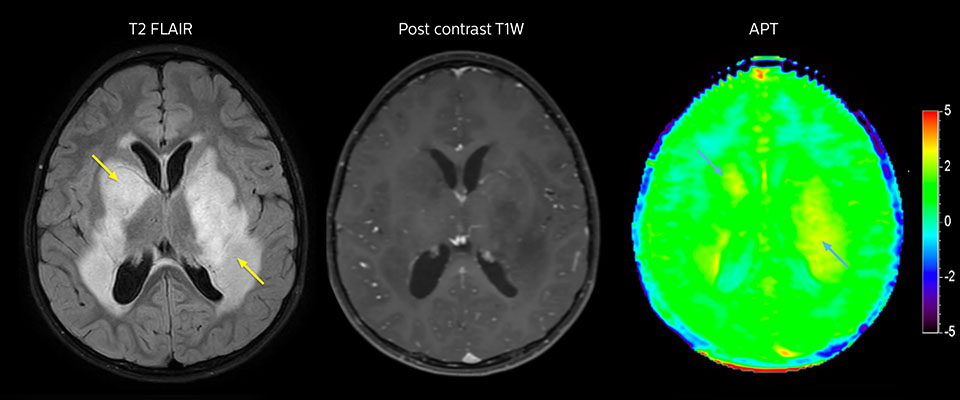

APT imaging of low-grade tumor

Low-grade glioma in a 5-year-old patient with neurofibromatosis 1. This low-grade lesion does not enhance on the post-contrast images, but does show an intermediate APT signal. The lesion stability over time confirms that it is a low-grade pathology.

Follow-up over time